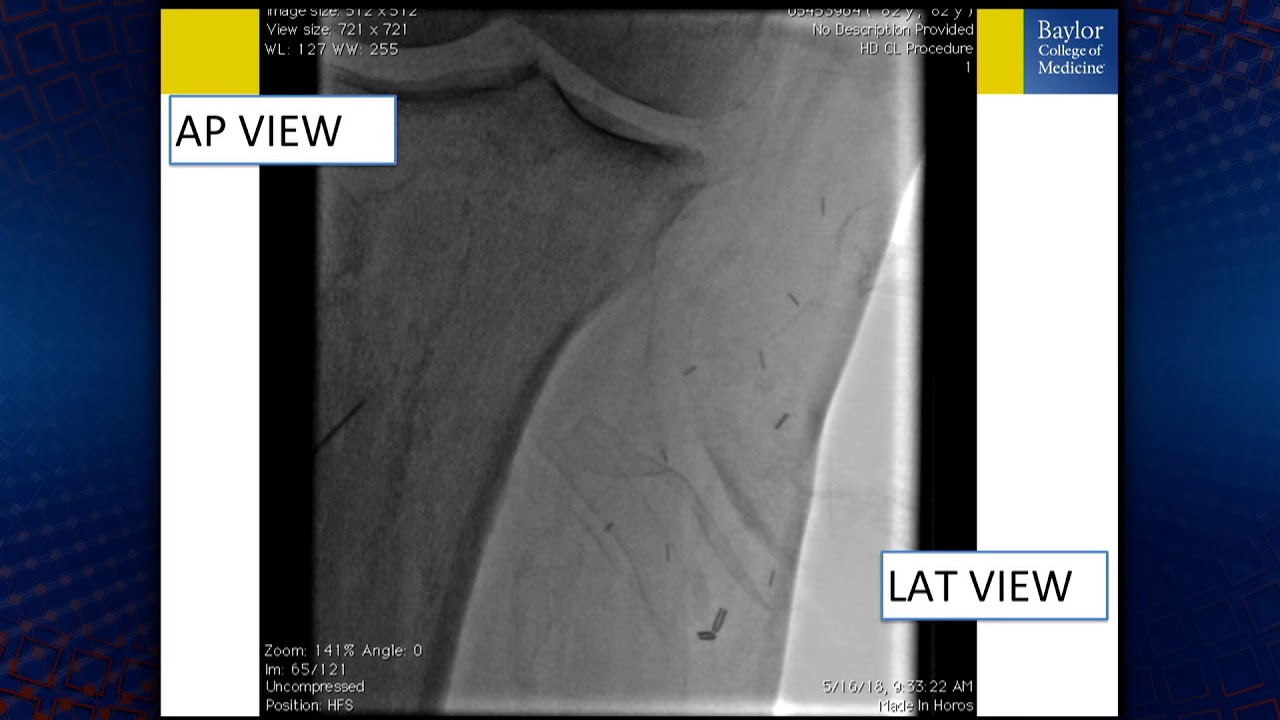

BTK Total Occlusion Crossing: How I Choose My Wires

Описание: BTK Total Occlusion Crossing: How I Choose My Wires